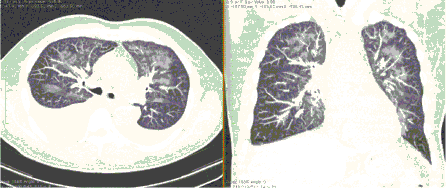

4.3. ЛУЧЕВАЯ ДИАГНОСТИКА COVID-19

Методы лучевой диагностики применяют для выявления COVID-19 пневмоний, их осложнений, дифференциальной диагностики с другими заболеваниями легких, а также для определения степени выраженности и динамики изменений, оценки эффективности проводимой терапии.

Стандартная РГ имеет низкую чувствительность в выявлении начальных изменений в первые дни заболевания и не может применяться для ранней диагностики. Информативность РГ повышается с увеличением длительности течения пневмонии. Рентгенография с использованием передвижных (палатных) аппаратов является основным методом лучевой диагностики патологии ОГК в ОРИТ. Применение передвижного (палатного) аппарата оправдано и для проведения обычных РГ исследований в рентгеновском кабинете. В стационарных условиях относительным преимуществом РГ в сравнении с КТ являются большая пропускная способность. Метод позволяет уверенно выявлять тяжелые формы пневмоний и отек легких различной природы, которые требуют госпитализации, в том числе направления в ОРИТ.

КТ имеет высокую чувствительность в выявлении изменений в легких, характерных для COVID-19. Применение КТ целесообразно для первичной оценки состояния ОГК у пациентов с тяжелыми прогрессирующими формами заболевания, а также для дифференциальной диагностики выявленных изменений и оценки динамики процесса. КТ позволяет выявить характерные изменения в легких у пациентов с COVID-19 еще до появления положительных лабораторных тестов на инфекцию с помощью МАНК. В то же время, КТ выявляет изменения легких у значительного числа пациентов с бессимптомной и легкой формами заболевания, которым не требуется госпитализация. Результаты КТ в этих случаях не влияют на тактику лечения и прогноз заболевания при наличии лабораторного подтверждения COVID-19. Поэтому массовое применение КТ для скрининга асимптомных и легких форм болезни не рекомендуется. При первичном обращении пациента с подозрением на COVID-19 рекомендуется назначать КТ только при наличии клинических и инструментальных признаков дыхательной недостаточности (SpO2 < 95%, ЧДД > 22).